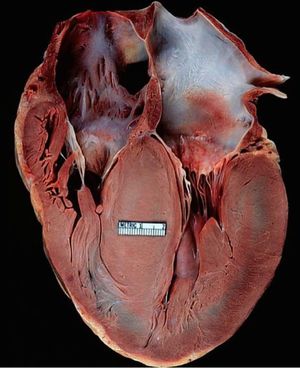

Left ventricular hypertrophy